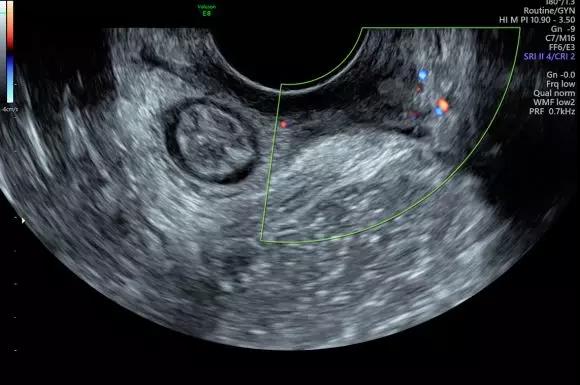

Voluson E8超聲儀:

廣泛應(yīng)用于婦產(chǎn)超聲臨床領(lǐng)域,尤其在產(chǎn)科、不孕不育生殖醫(yī)學(xué)和女性盆底功能障礙性疾病等領(lǐng)域,提供高品質(zhì)圖像及專業(yè)的婦產(chǎn)超聲臨床解決方案。

案例圖

女性不孕檢查

女性產(chǎn)后盆底功能檢查